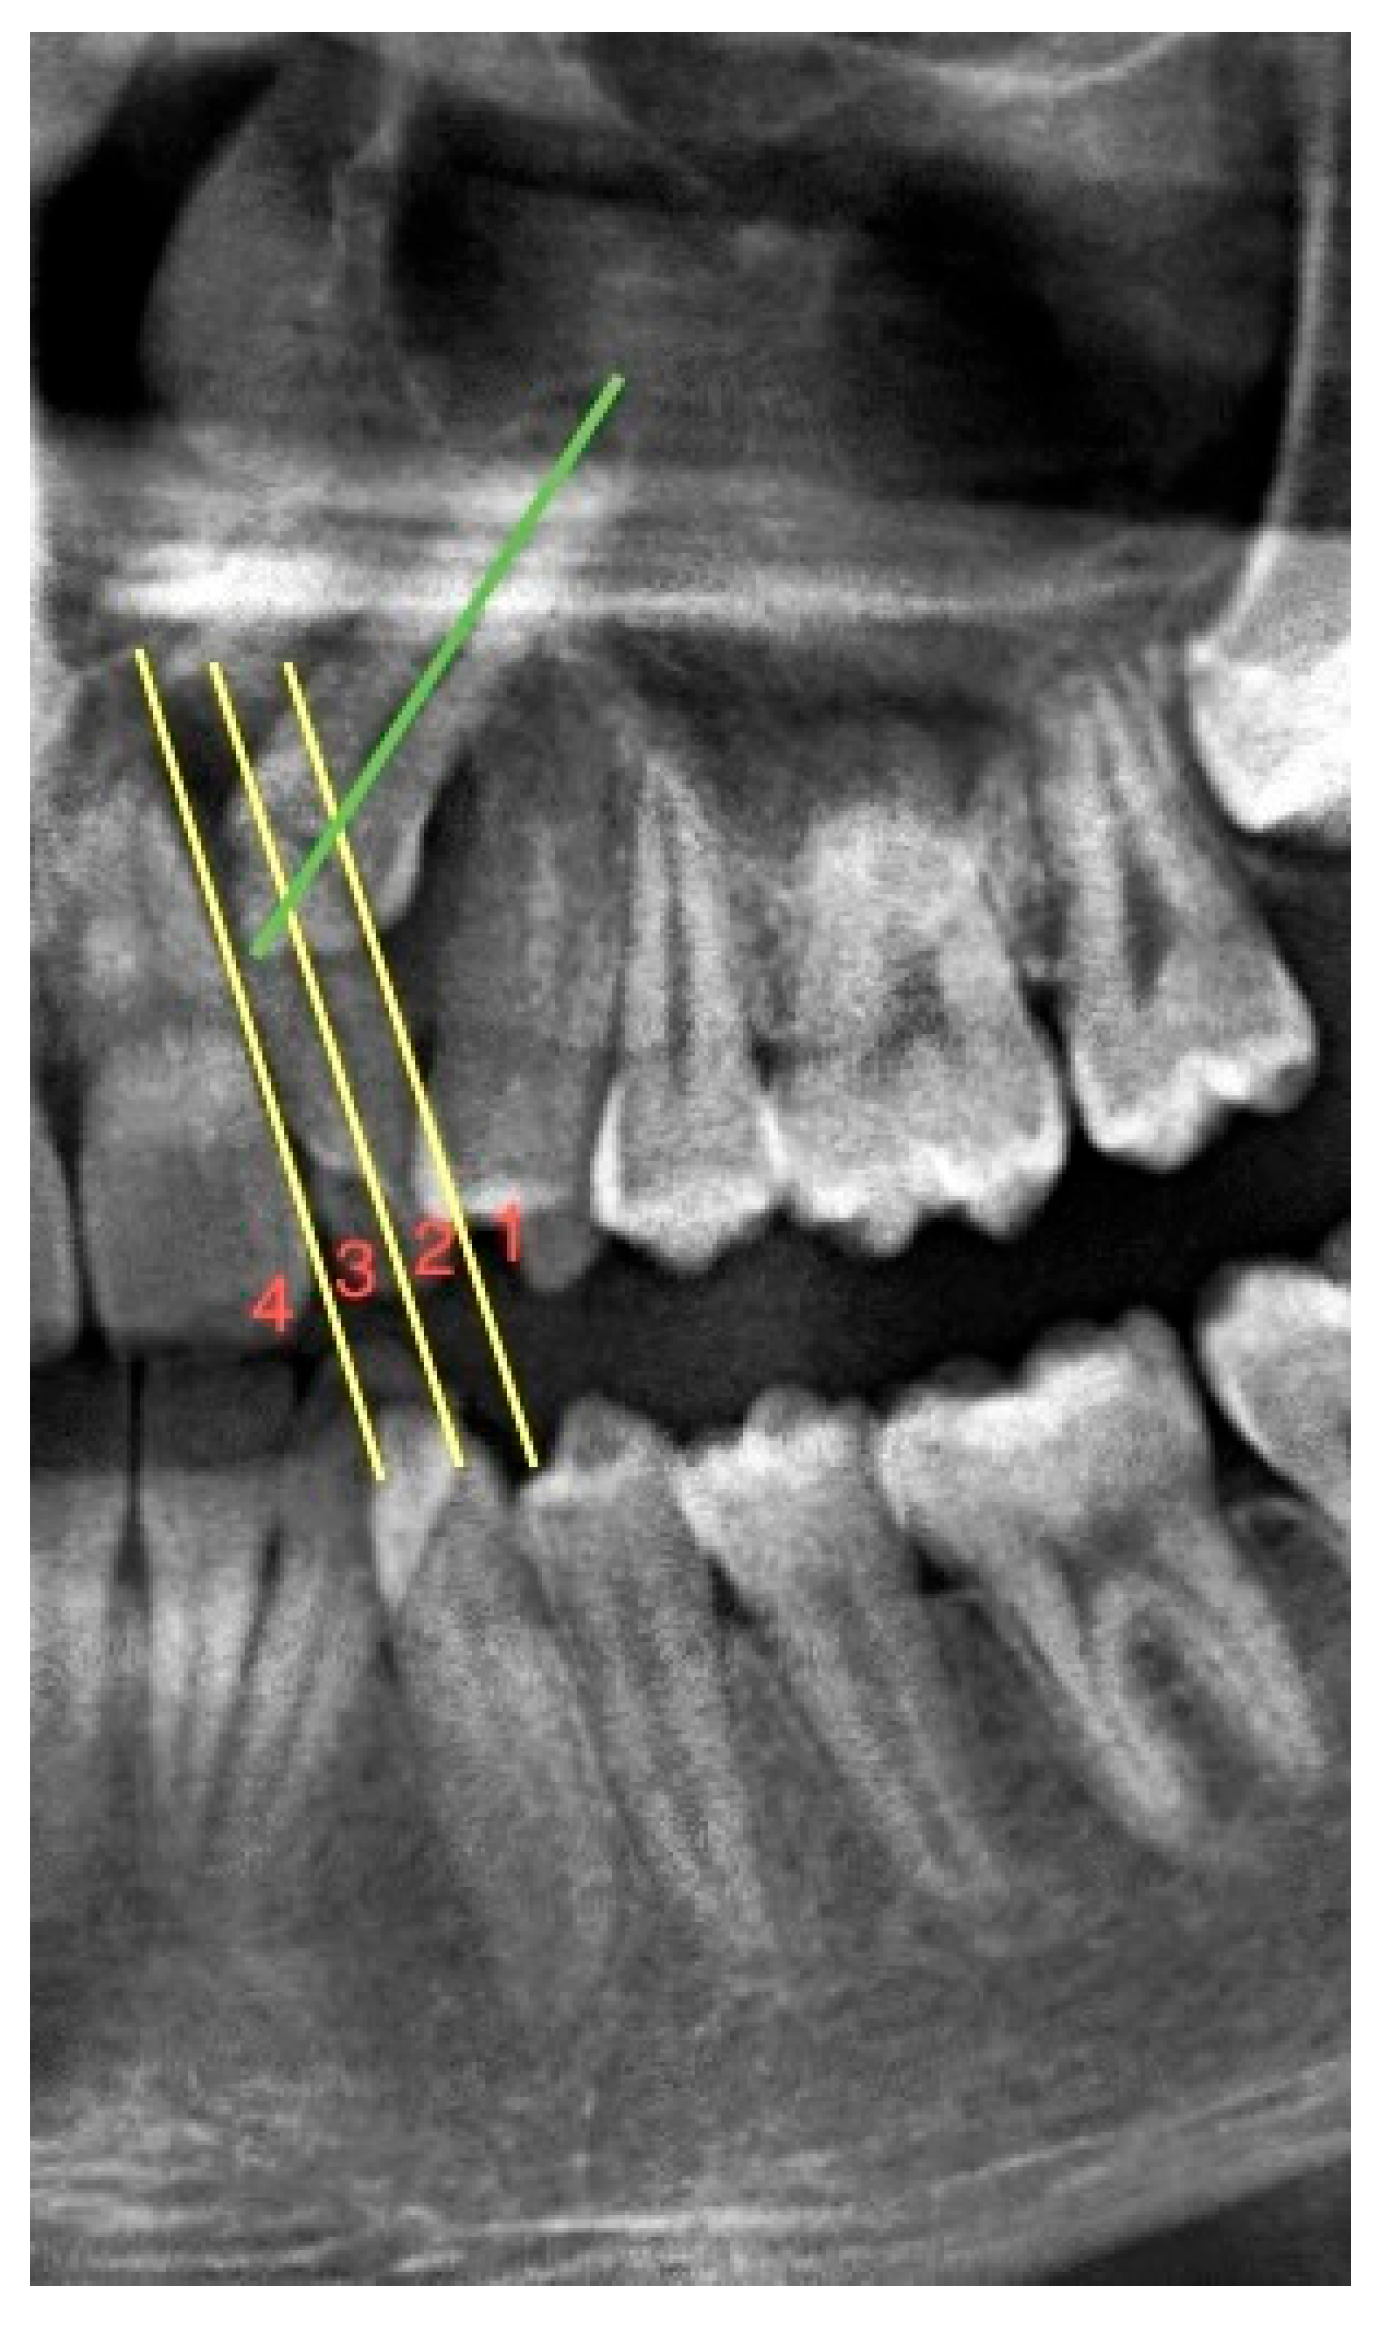

To determine the mesiodistal position of the impacted maxillary canines, the sector classification used by Lindauer et al. [21] concerning the permanent lateral incisors was used. Three vertical lines divide the lateral tooth and its surroundings into four sectors. The first of these lines passes through the center of the lateral tooth. The second line passes through the mesial root surface of the lateral tooth, and the third line passes through the distal root surface. In this way, impacted maxillary canines were classified according to these regions as sectors 1, 2, 3, and 4 from distal to mesial (see Figure 1).

Figure 1.

A section from the panoramic radiograph showing the sector classification of the impacted maxillary canine relative to the root of the lateral tooth. Green line: long axis of the impacted maxillary left canine. Yellow line: it divides the maxillary lateral incisor into 4 separate regions parallel to its long axis. (Sector classification of this impacted maxillary left canine is 3).